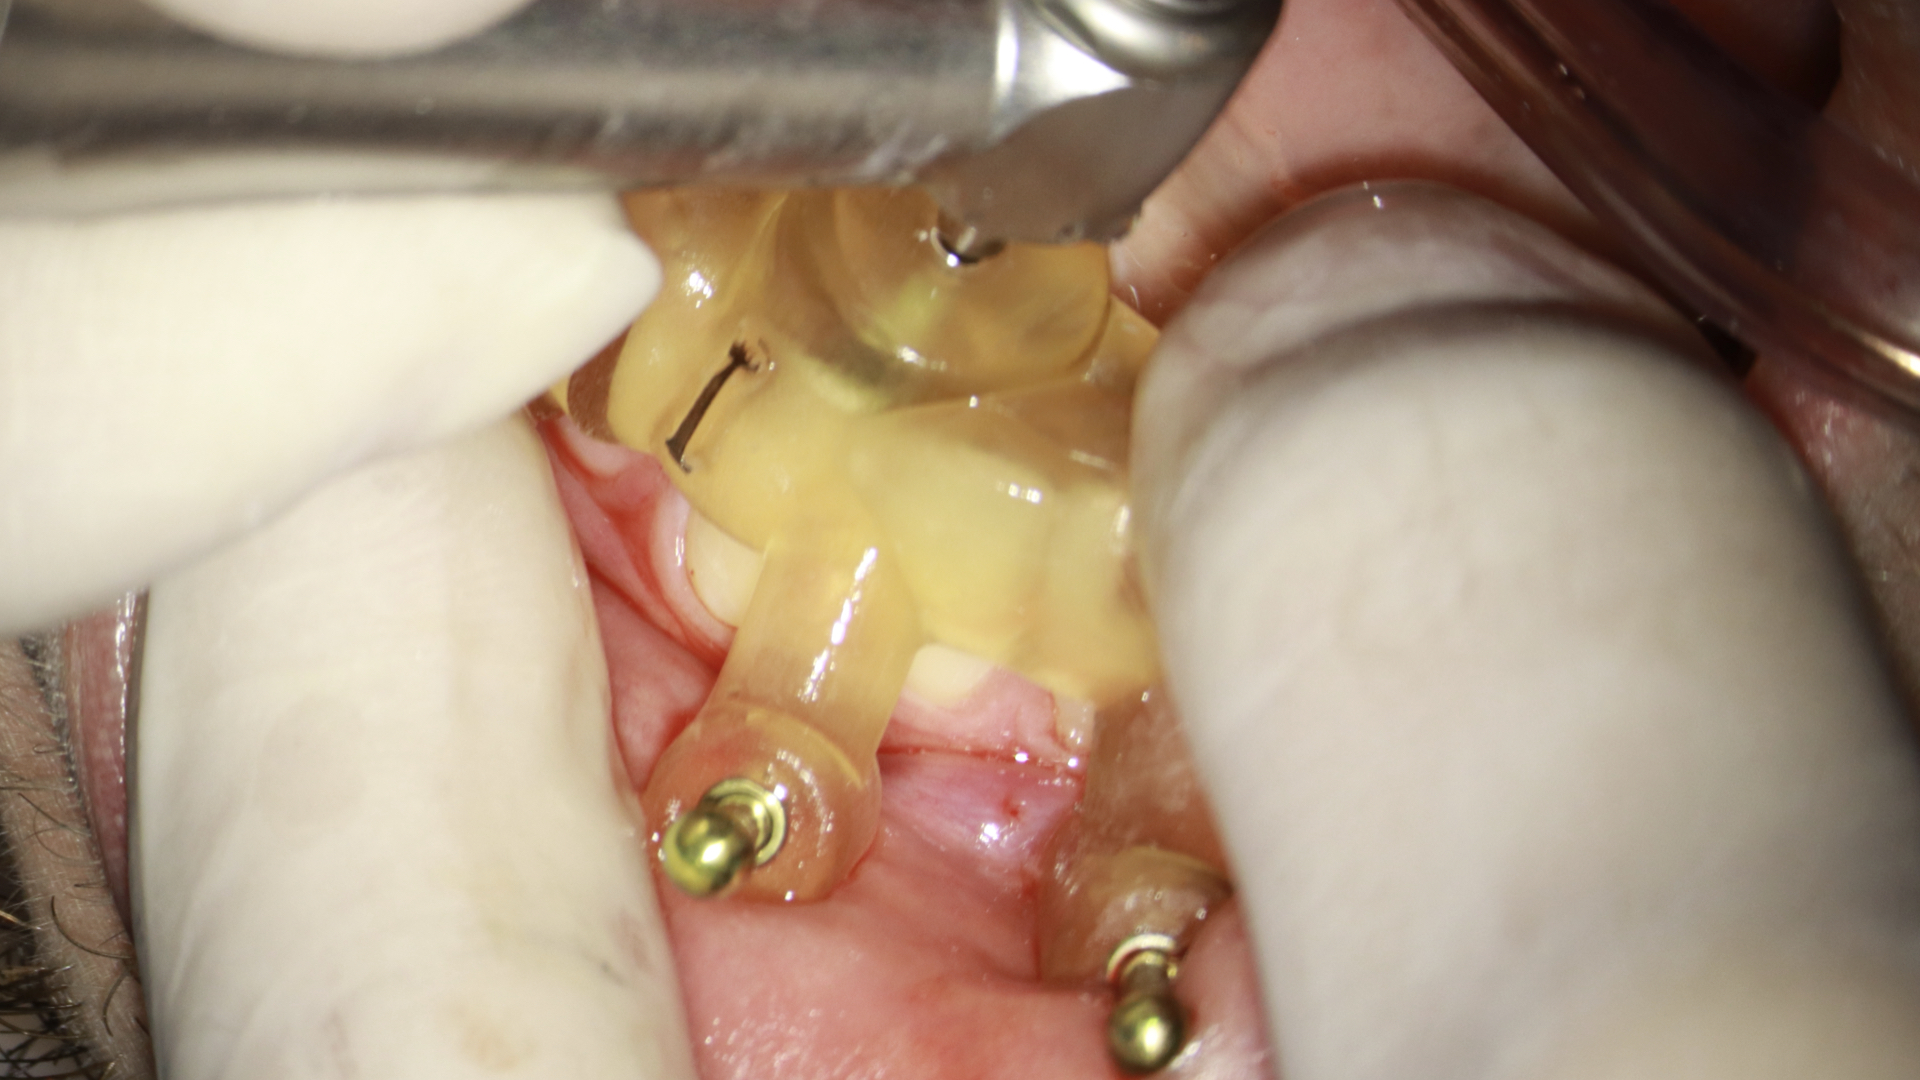

- Fixar o endoguide na arcada que necessita de tratamento com os fixadores. Estas anilhas usadas para a colocação da fresa e fixadores são metálicas. Para fazer está fixação é necessário o uso da fresa em osso. Você pode usar um motor endodôntico na máxima rotação e torque irrigando durante o procedimento ou um motor de implante que já tem a irrigação acoplada e facilita esta perfuração. A vantagem do motor de implante é que você consegue fazer a perfuração em osso com maior torque, o que possibilita que em caso de perfuração em mandíbula, com osso mais compacto, tenhamos um procedimento mais tranquilo (figura 7, 8 e 9).